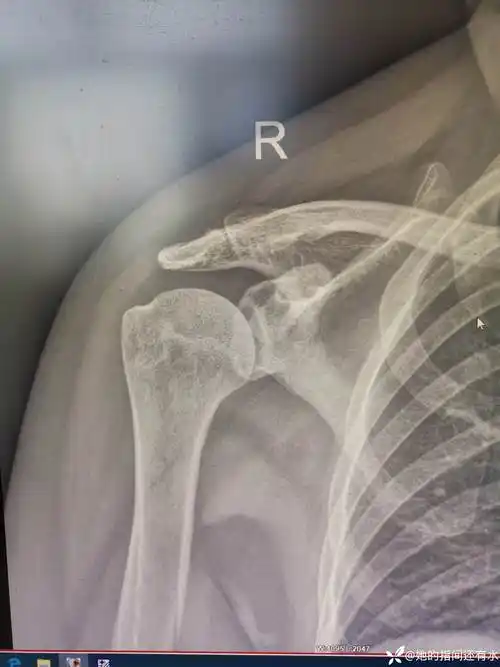

肩关节半脱位